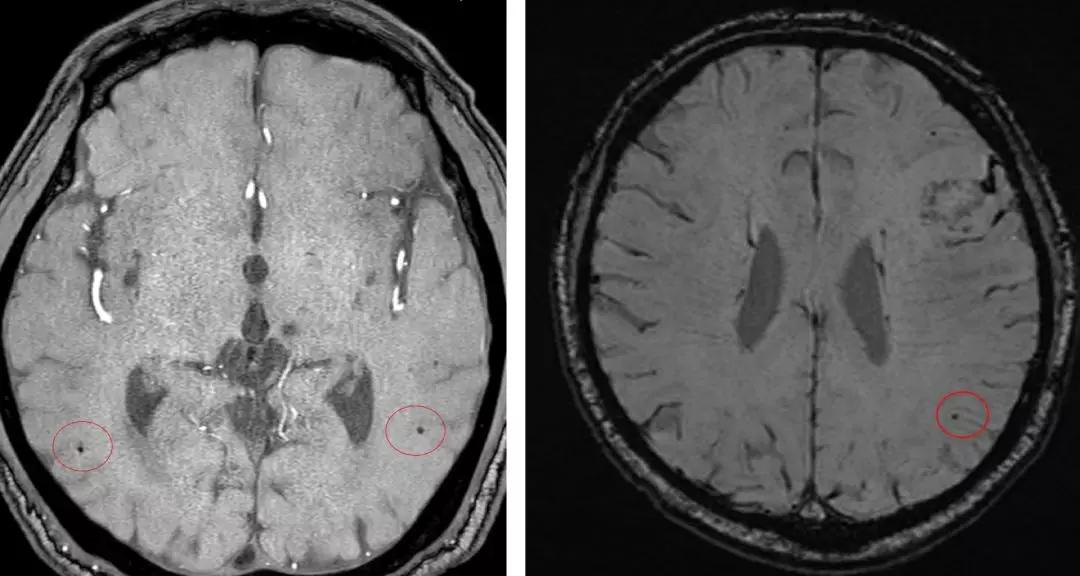

因此,考虑可能是其他原因增加了患者溶栓后出血转化的风险。随后进一步发现:患者多模 MR 上提示存在典型的脑小血管病影像学征象。

脑白质病变(左)血管周围间隙(右)

腔隙性脑梗死

脑微出血